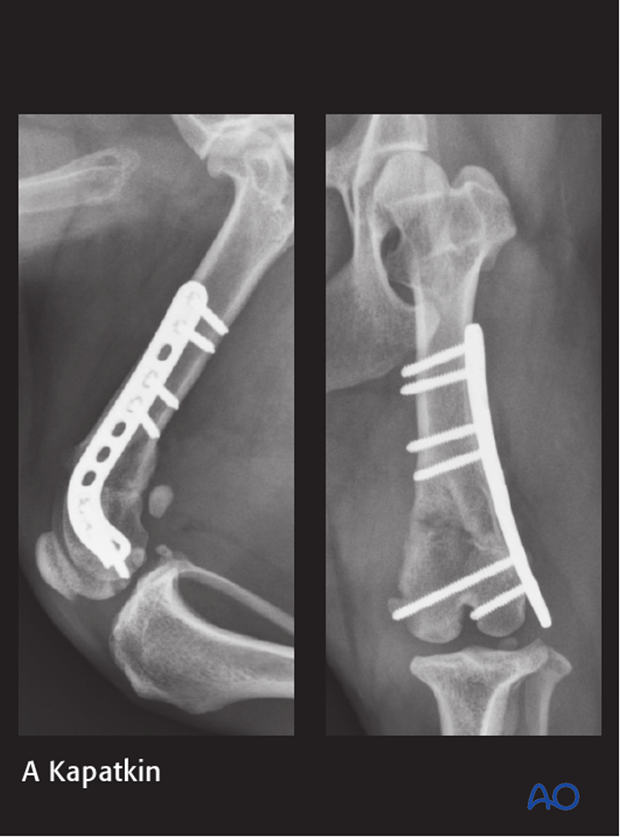

10-year-old MC Jack Russell Terrier of 6 kg.

Stepped on by owner 1 week before presentation.

The fracture was repaired using a 2.0 mm distal femoral plate in bridging fashion.

7-week postoperative radiographs.

The patient reported fully healed at the 12-week postoperative radiographic control.